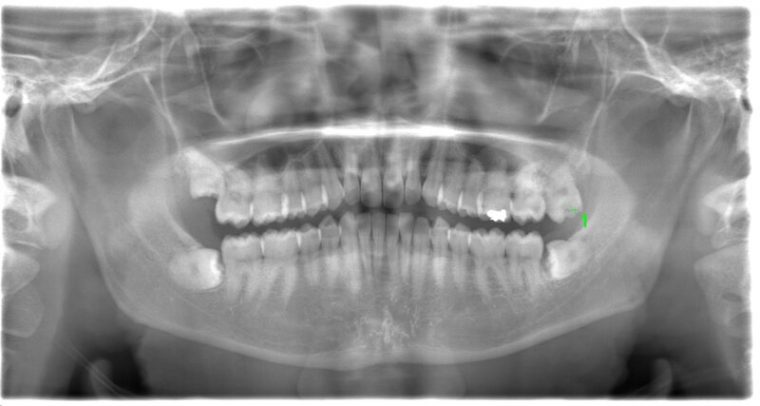

CASE 1

| 年齢・性別 | 30代・女性 |

| 主訴 | 左右に分けて親知らずを抜きたい、できれば痛くなく抜きたい |

| 親知らずのはえ方 | 完全に出ていてまっすぐはえている |

| 抜歯期間 | 15分 |

| 抜歯費用 | 約2,000円(保険内) |

| 抜歯内容 |

何度か虫歯になり痛みはないが早めに抜きたい。 完全に頭が出ているため歯ぐきを切ったり骨を削らずに抜歯しました。 根の形も単純なため抜歯自体は5分もかからず上下ともに終わりました。 術後痛みや腫れも出ていません。 抜歯後は感染をしやすいため必ず抗生物質を飲み切ってください。 |